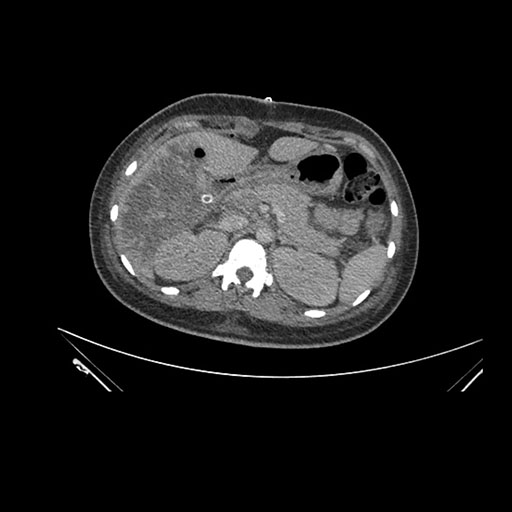

Axial Venous